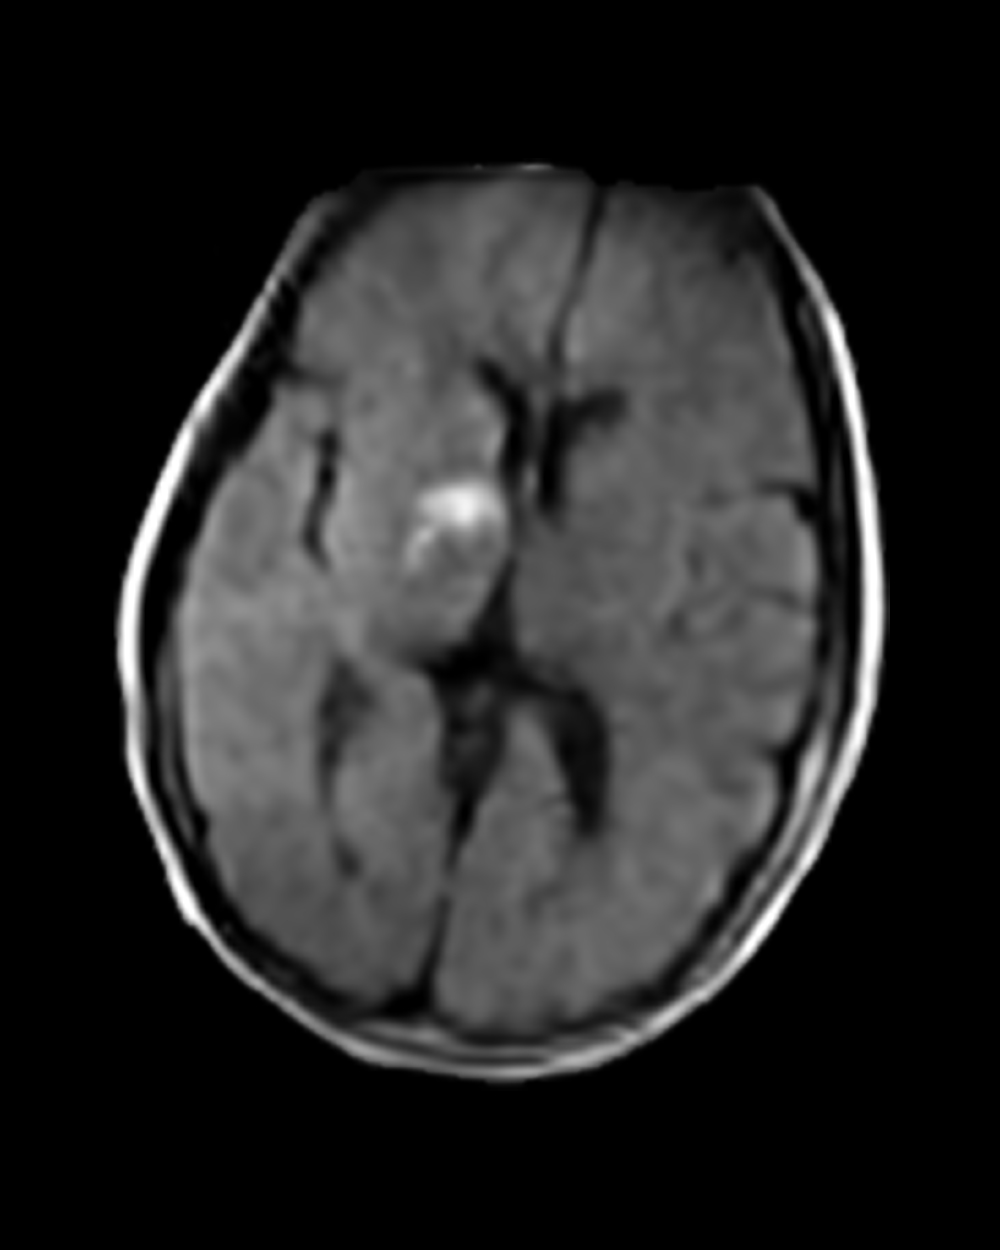

Right Anterior Choroidal Infarct

Patient Profile

63-year-old patient with a history of diabetes and hypertension. Presented to the ED with acute-onset left-sided weakness and sensory disturbance involving the face and extremities.

Portable MRI

The Swoop system was driven to the patient’s bedside and ready to scan within minutes

Stroke Detected

Swoop system images allowed clinicians to confirm infarcts

Triage

Patients were triaged to stroke units for management and monitoring